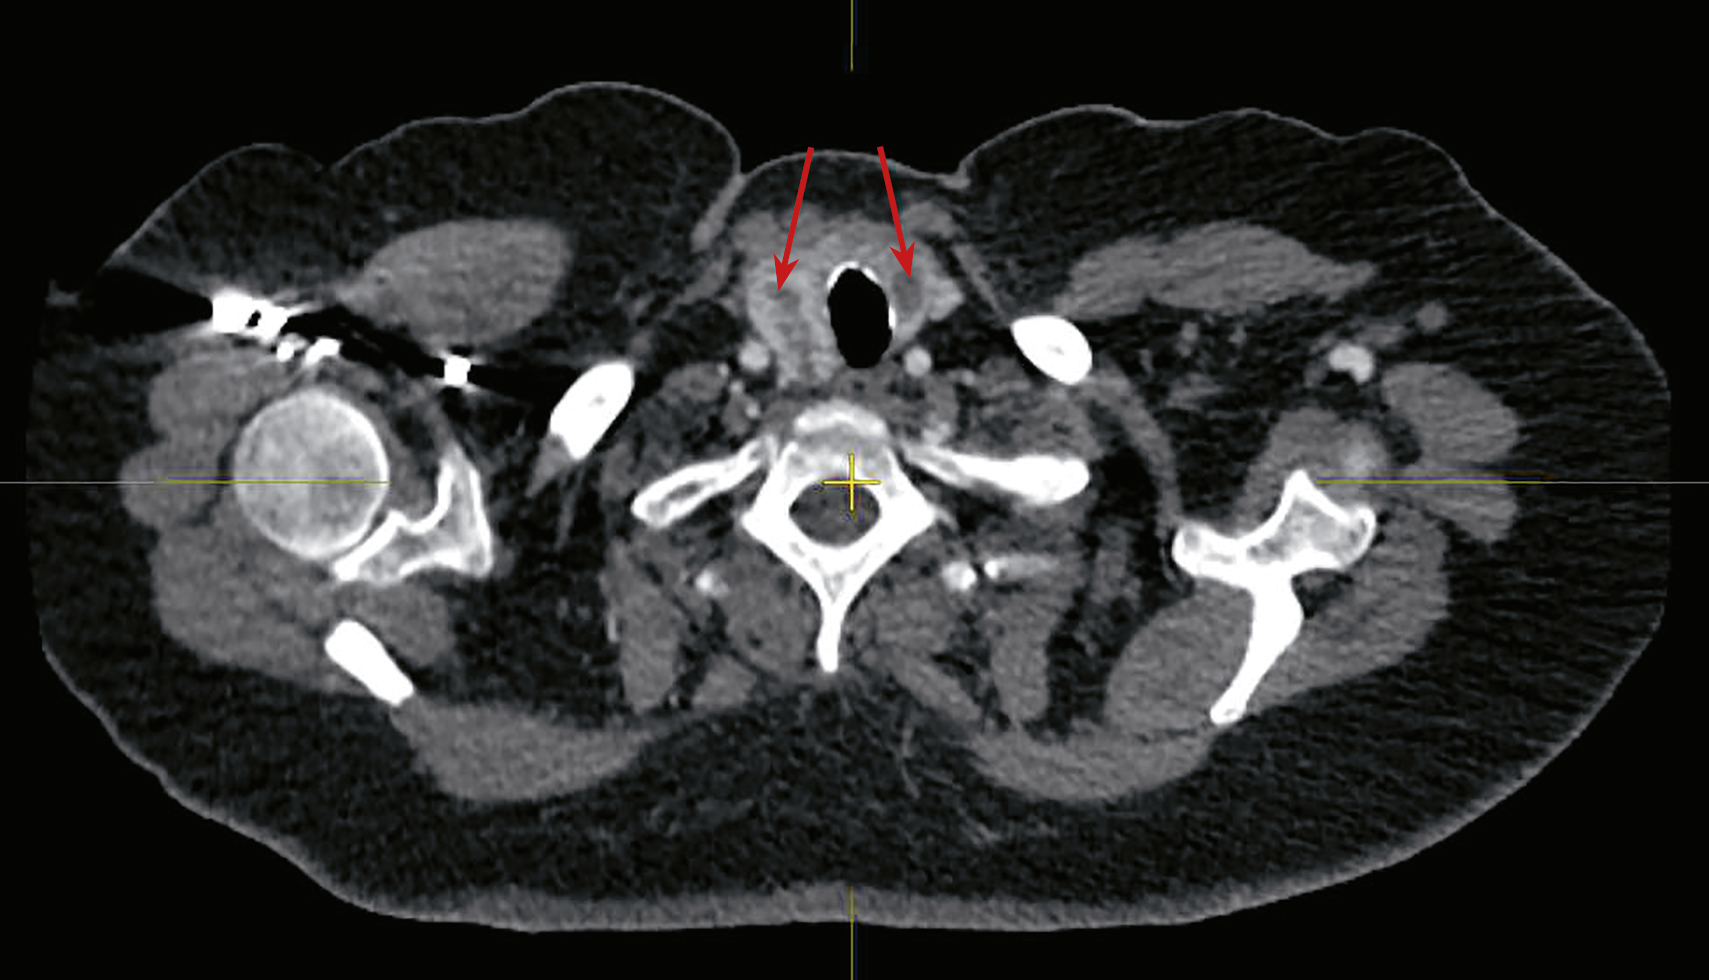

2. Рисунок 2. Фолликулярная аденома щитовидной железы (аксиальный срез, образование указано стрелкой). А — натив, В — артериальная фаза. | |